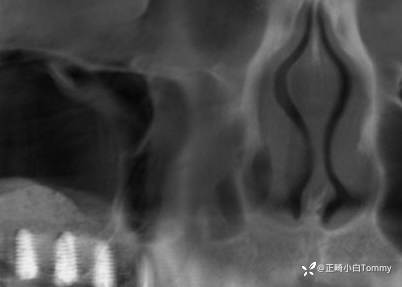

术后CBCT,未损伤窦底黏膜,白色影像是植入的骨粉